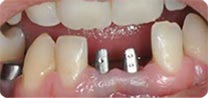

安卓健临床案例分享

安卓健种植产品销往全球100多个国家精密工程CFDA

权威认证,可放心使用。安卓健种植体手术程序简单,

更少创伤,更快恢复,更加安心。